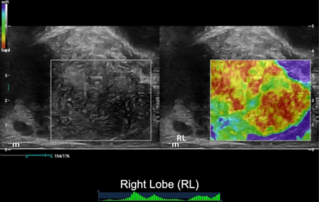

??? ?? ??? ?? ???? ? ??? ?? ??? ?? ??? ??? ??? ???. ???? ??? UWN+ ?? ?? ??? ?? MI??? ??? ??? ?? ?? ??? ?? ?? ?? ???, ?? ?? ?? ???? ??? ? ????.